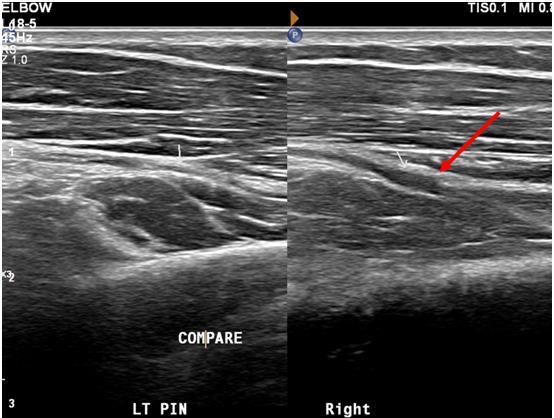

NERVE IMPINGEMENT SYNDROMES:

Radial nerve impingement / cubital tunnel syndrome can be associated with anterior elbow pain

Fig. 13 Longitudinal ultrasound images of anterior left and right elbow showing normal thickness posterior interosseous nerve (PIN) on left (white arrow), but a thickened right PIN (red arrow) at the margin of the Arcade or Frohse (not shown).